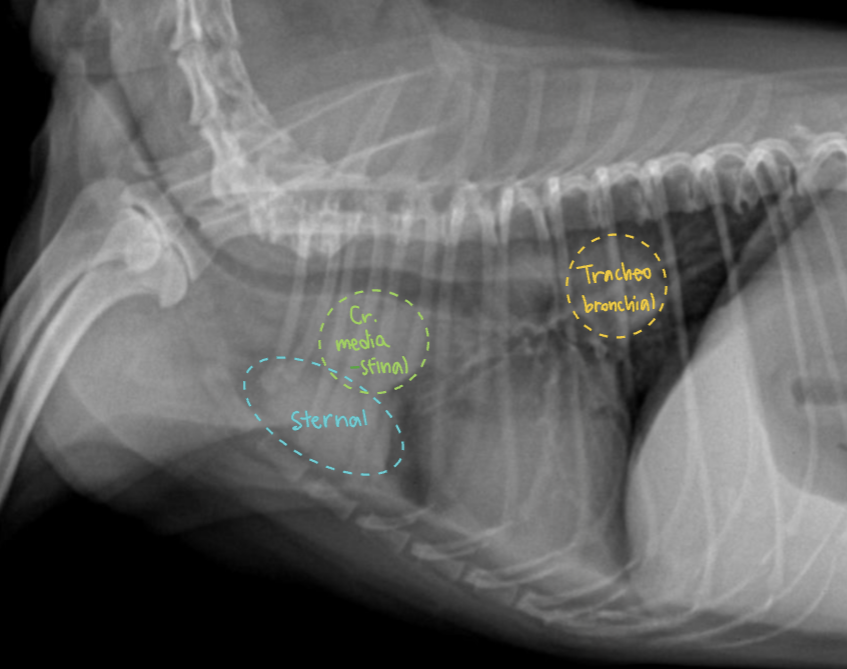

3. Mediastinal lymph nodes (도식화 필요)

(셋 다 비대되어 있음)

• Cranial mediastinal LN (전종격 림프절)

• Sternal LN (흉골 림프절) : 2번째 sternum 등쪽, 1개 또는 여러개

• Tracheobronchial LN (기관기관지 림프절) : carina 근처 2-3개, 인접한 trachea 압박할 수 있음

• Cr. mediastinal, Tracheobronchial : 흉강 문제 있을 때 비대

• Sternal : 복강 문제 있을 때 비대